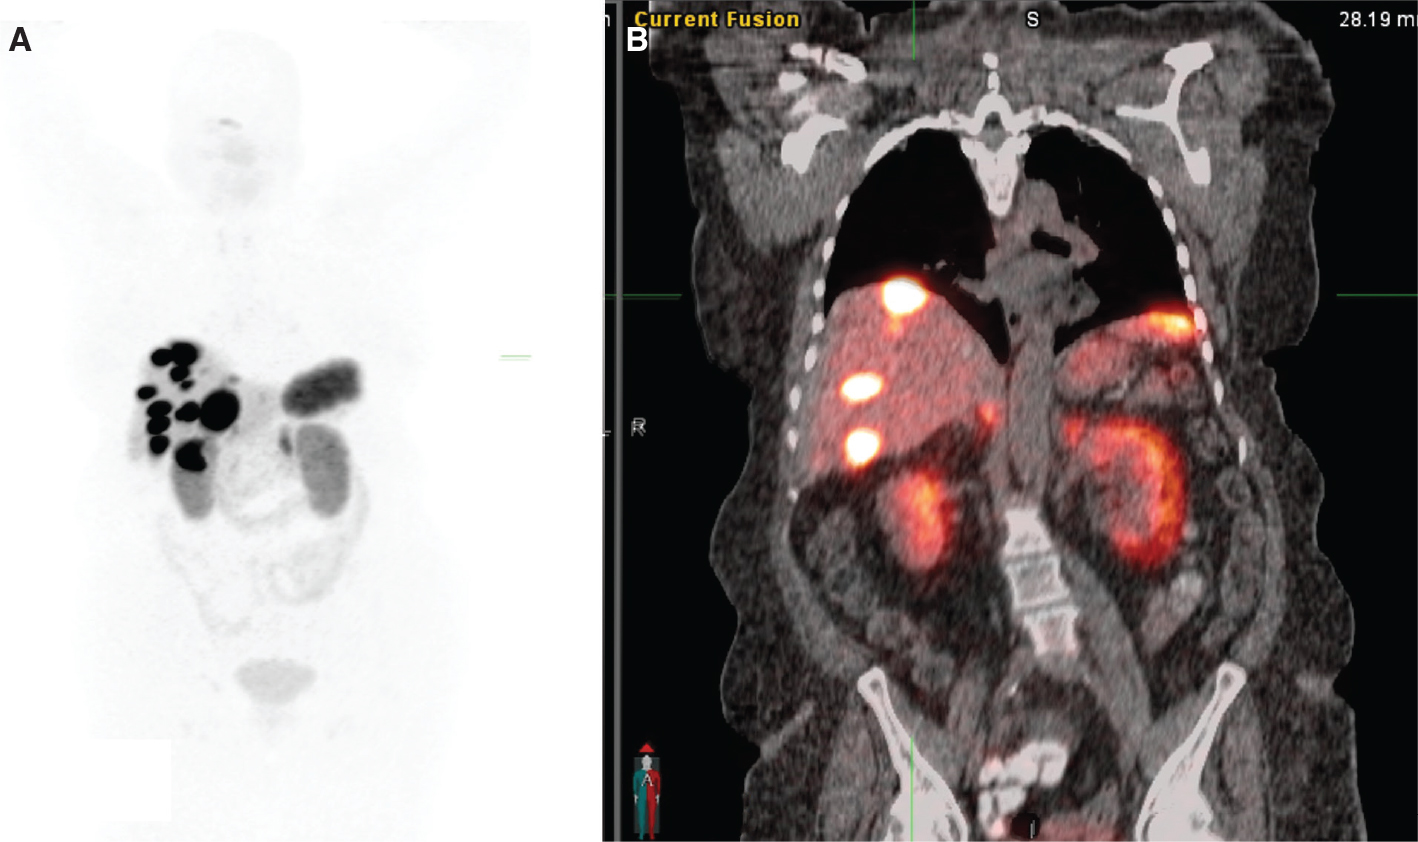

Patients are evaluated by a multidisciplinary NET team, including a medical oncologist, an oncological surgeon, and a nuclear medicine physician (who must be an authorized user) to decide on the appropriateness and timing of PRRT in individual patients. Ideal candidates for PRRT include patients with well-differentiated and moderately-differentiated neuroendocrine carcinomas defined as NET grade 1 or 2 according to the recent WHO 2010 classification (39). Patients considered for PRRT should undergo diagnostic somatostatin receptor imaging such as SSTR PET scan or SSTR scintigraphy (111In-pentetreotide) to demonstrate adequate SSTR expression (40) (Figure 4). The two FDA approved SSTR positron emission tomography (PET) imaging agents are Gallium-68 (68Ga) DOTATATE and Copper-64 (64Cu) DOTATATE. These diagnostic imaging agents constitute diagnostic components of PRRT Theranostics.

Fig 4

Figure 4. A 74-year-old female with advanced and inoperable metastatic ileal NET. A. 68Ga-DOTATATE (SSTR PET) MIP image and B. Fused coronal image show multiple intensely somatostatin receptor-rich tumors in the liver and portocaval lymph node.